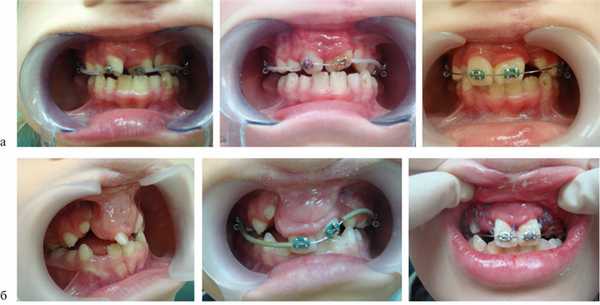

По окончании периода ретенции ортодонтическое лечение было направлено на нормализацию положения зубов, формирование оптимальной окклюзии (рис. 5, а—г).

Рис. 5. Этапы ортодонтического лечения по окончании периода ретенции. а — до костной пластики; б—г — перемещение небно расположенного бокового резца в костный регенерат; д, е — имплантат в области костного регенерата.

При адентии бокового резца в область костного регенерата вводили имплантат (см. рис. 5, д, е).